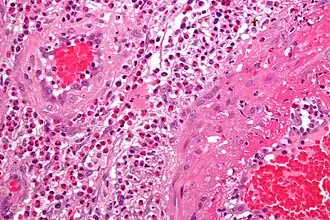

Le diagnostic définitif de vascularite est établi après une biopsie des organes ou des tissus impliqués, tels que peau, sinus, poumon, nerf et rein. La biopsie met en évidence le type d'inflammation des vaisseaux sanguins.

Exemple illustré : vascularites leucocytoclastiques